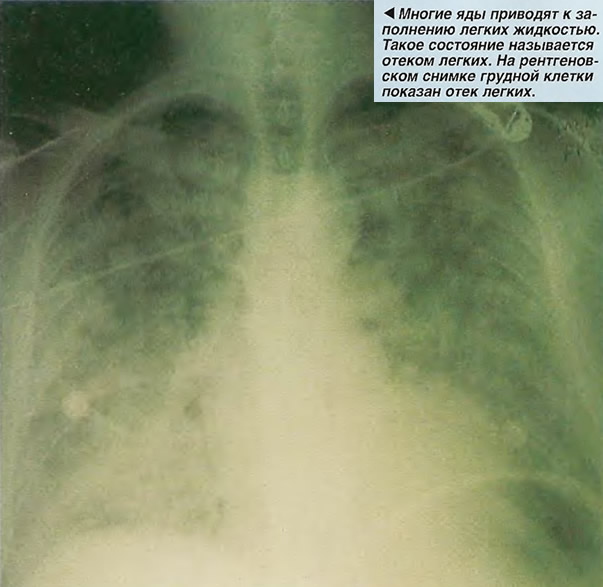

Симптомы и причины скопления воды в легких

Раздел: Ракурсы просвещения